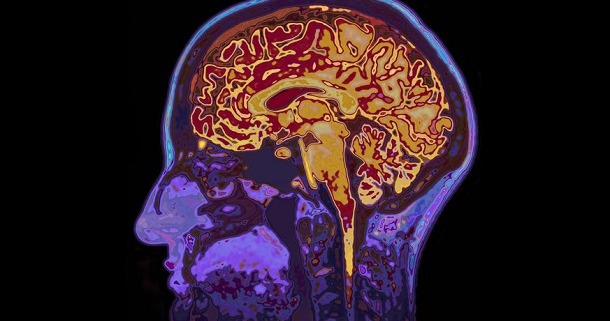

Eine britische Studie kam zu dem Ergebnis, dass eine schwere Corona-Infektion das Gehirn langfristig schädigen kann. Die Forscher stellten fest, dass viele COVID-Patienten noch 12 bis 18 Monate nach einem Krankenhausaufenthalt schlechtere kognitive Leistungen aufwiesen als gesunde Vergleichspersonen.

Scans zeigten eine Reduktion des Gehirnvolumens in bestimmten Bereichen.

Es wurden überhöhte Werte von Hirnverletzungsproteinen im Blut festgestellt.

Die kognitiven Defizite waren mit einer Alterung des Gehirns um 20 Jahre vergleichbar.